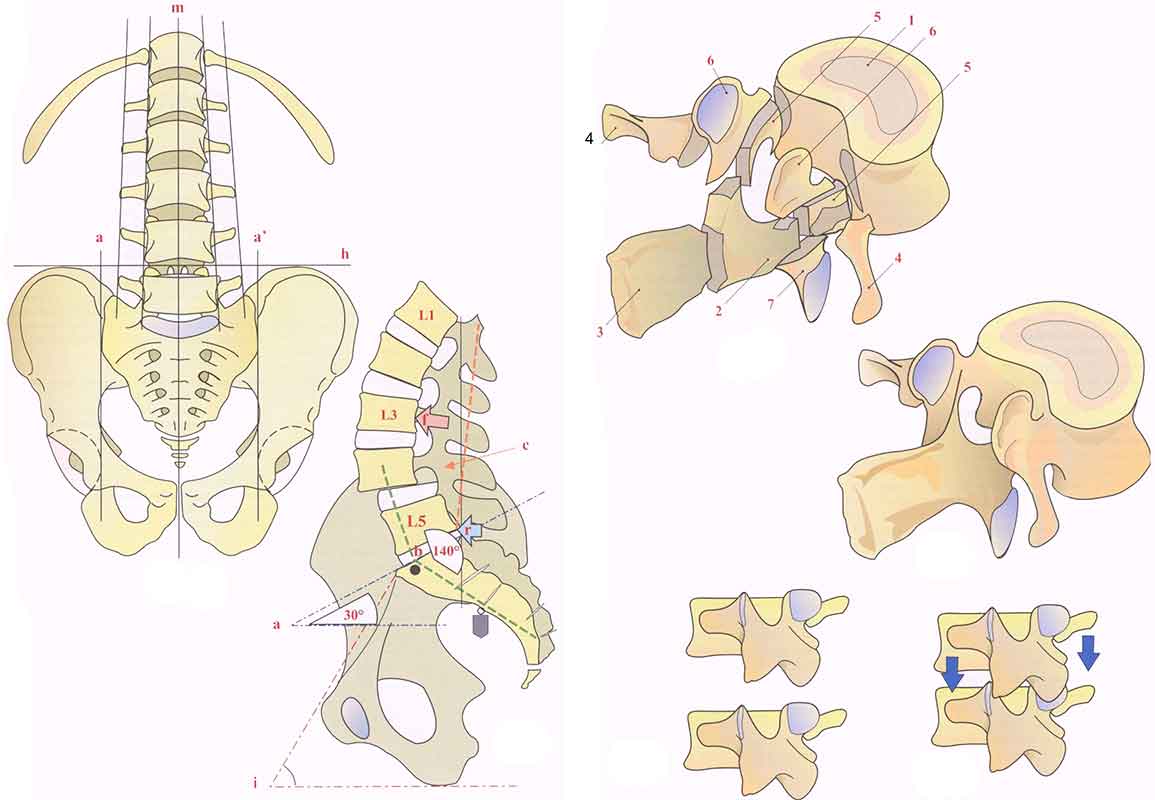

Структура позвоночника: сегменты и тазовые отделы в фотографиях